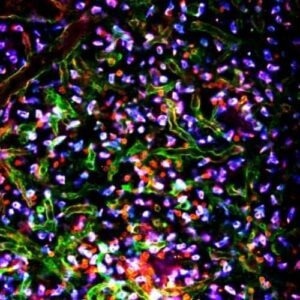

IVIM Tech imaging gallery

Lymph Node. Image Credit: Scintica Instrumentation Inc.

Lung. Image Credit: Scintica Instrumentation Inc.

Bone Marrow. Image Credit: Scintica Instrumentation Inc.

Skin. Image Credit: Scintica Instrumentation Inc.

Cancer Xenograft. Image Credit: Scintica Instrumentation Inc.

Cancer Metastasis. Image Credit: Scintica Instrumentation Inc.

Drug Distribution. Image Credit: Scintica Instrumentation Inc.

Cancer Drug Delivery. Image Credit: Scintica Instrumentation Inc.